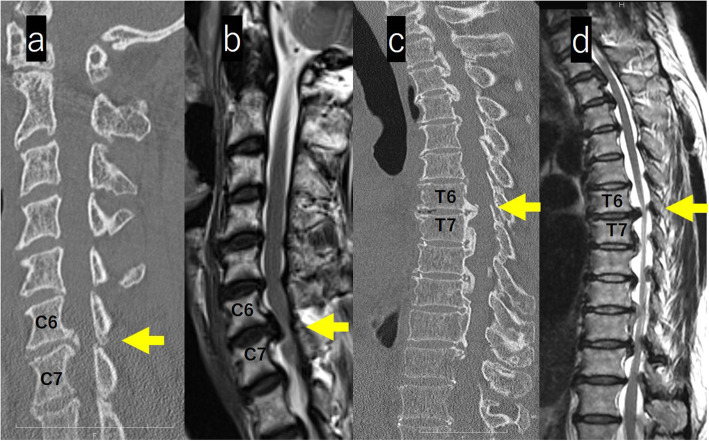

On computed tomography (CT) images of the whole spine, isolated OPLL was observed from the lower cervical vertebra to the middle thoracic vertebra. At T6/7, a beak-shaped protrusion into the spinal canal was observed (Figs. 3a, c).

Fig. 3.

a-d: MRI and CT images of the cervical and thoracic spine. CT images of the whole spine, isolated OPLL was observed from the lower cervical vertebra to the middle thoracic vertebra. At T6/7, a Beak-shaped protrusion into the spinal canal was observed (a, c). MRI revealed stenosis with a spinal cade intensity change at C6/7 and extensive spinal cord compression with a spinal cade intensity change in the thoracic spine (b, d)

Magnetic resonance imaging (MRI) of the whole spine revealed stenosis with an intensity change in spinal cord at C6/7 and extensive spinal cord compression in the thoracic spine (Figs. 3b, d). Contrast-enhanced MRI of the brain showed a mass without contrast enhancement on the right side of the anterior pituitary gland (size, 10 mm × 12 mm × 10 mm) with suprasellar and parasailer extension; the image revealed a pituitary macroadenoma (Fig. 4).